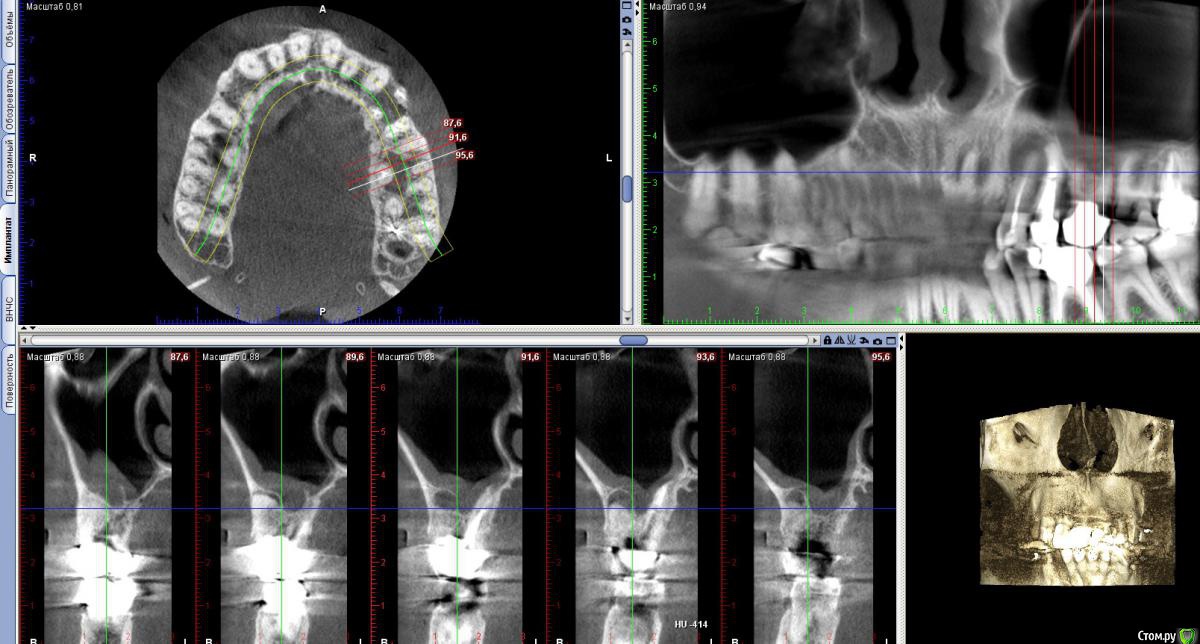

vitavita Опубликовано 4 февраля, 2015 Поделиться Опубликовано 4 февраля, 2015 Начну историю о 6 зубе с самого начала. Когда то давно - лет 30 назад , в советское время мне его кто то лечил , уже не помню кто и как, школьником был. Видимо были удалены нервы. Он меня не беспокоил практически никогда. На обычных ортопанорамных снимках ничего не видно было. 11 лет назад , перед тем как ставить на него коронку , мой доктор пытался пройти каналы, удалось только у принебноого пройти а у 2-х внешних не удалось . Долго пытался , сверла грелись и изнашивались. Сказал что материал там как стекло. Что если когда нибудь заболит то надо будет операцию делать сбоку для резекции корней. Шло время - зуб не болел , я на него нормально жевал и жую до сих пор. Вспоминаю только как то года 3 назад очень жесткое что то попалось и поболел пару дней и прошел. Не придал значения. И вот в ноябре 2014 у меня вдруг обнаружилась киста но на 4-м верхнем левом зубе - нарвало после небольшого ударо по нему сбоку. Хотя ничего не болело. Пошел естественно к врачу . На обычном ортопанорамном снимке толком не видно было. Поэтому отправил доктор меня на томограмму по поводу 4-го зуба и заодно и 6-го , т.к. помним что каналы там не были пройдены. И вот 21 ноября сдел томограмму (если интересно https://yadi.sk/d/Th2NbfMSeULRo). И на ней увидили большую кисту за 4 зубом и кисту у 6-го. Доктор предложил мне удалить 4-й , сделать резекцию 6-го с возможным синус-лифтингом и небольшую резекцию 5-го. И все это одновременно. Напугал возможным гайморитом с очень тяжелыми последствиями. Расстроившись я пошел к другому знакомому хирургу в один из стоматологических институтов. Он предложил сразу сделать резекцию 4-го зуба . Она была удачно проведена открытым способом. 2 месяца походил с йодоформной турундой (менял каждые 10 дней) . Все практически заросло. Теперь спустя 2 месяца встал вопрос о 6 зубе- как с ним быть. Посмотрев томограмму , посоветовашись с другим врачем сказал что все таки резекцию здесь делать нецелесообразно , т.к резать придется 2 корня под корешок , от зуба мало что останется и он долго не простоит. Не жилец. Надо удалять и потом как то протезировать. Послал к терапевту - может можно пройти . Терпавт сказал что для этого надо снимать коронку , но зуб то не болит. Ситуация дурацкая. Отправили к ортопеду , тот сказал что смысла снимать коронку нет , т.к. скорее всего лучше не сделают , а мучаться мне много и никакого результата. Зуб не качается , стоит твордо. И т.к через полгода мне повторно надо будет делать томограмму из-за 4 зуба , то посмотреть динамику развития и кисты и от этого делать выводы. На этом вроде остановились. Теперь у меня 2 выхода :1. или подождать полгода и потом скорее всего удалять2. идти к другому доктору и попытаться сделать резекцию 6-гоСтоит ли бороться за зуб , который к тому же не болит ? Ссылка на комментарий

vitavita Опубликовано 8 февраля, 2015 Автор Поделиться Опубликовано 8 февраля, 2015 Надо эндодонтически лечить все 3 зуба4-ому уже резекцию сделали , удалили кисту (большая была - 1см). Вроде такого размера только операцией можно удалить. 5-й тоже поскоблили заодно, но без резекции. Все уже заросло нормально за 2 месяца. Так что с этим уже проблем никаких не должно быть. А вот с 6-м проблема - доктор 11 лет назад пытался пройти каналы , но там стекло говорит. Непроходимые. Зуб под коронкой. Чтобы проверить можно ли пройти еще раз надо снимать ее. Ортопед отсоветовал - намучитесь, а пройти скорее всего не сможете. Велел наблюдать просто. Делать же резекцию один хирург говорит не надо , т.к. зуб не проживет долго , опираться уже не на что будет. А другой все таки предлагает сделать резекцию 2 корней с вычисткой кисты.Вопрос - насколько есть вероятность все таки попробовать пройти каналы если там что то вроде стекла? Может кто то посоветует в Москве действительно хорошего эндодонтолога ? Ссылка на комментарий